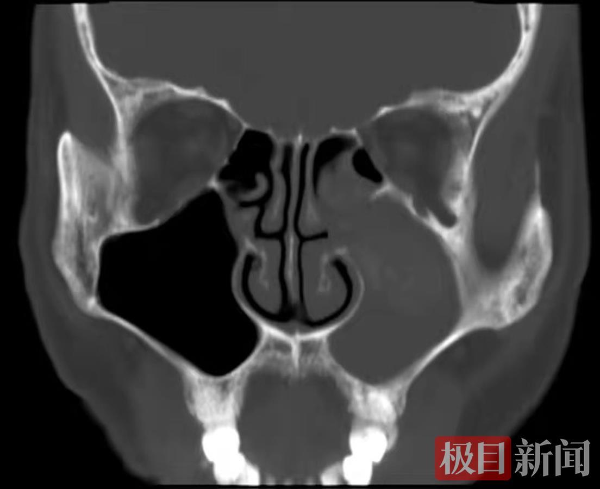

鼻子里也会长“石头”吗?当鼻腔鼻窦发生特异性感染时,就会形成类似石头的新生物,比如真菌性鼻窦炎。

术中,医生在刘先生鼻腔鼻窦内取出大量黑褐色干酪样真菌团块,经过细致的操作和反复检查,最终确定鼻腔鼻窦里的肿物被全部清理干净,术后病理确诊为毛霉菌感染。

据泰康同济(武汉)医院耳鼻喉科王美荣主任表示,真菌性鼻窦炎是鼻科临床常见的一种特异性感染性疾病,症状一般要比细菌性鼻窦炎重一些,表现为反复的鼻腔内脓臭鼻涕,严重的头痛及鼻塞等症状。真菌性鼻窦炎多在机体长期使用抗生素、糖皮质激素、免疫抑制剂或接受放射治疗等情况下发生,也可在一些慢性消耗性疾病如糖尿病、烧伤致机体抵抗力下降时发生。